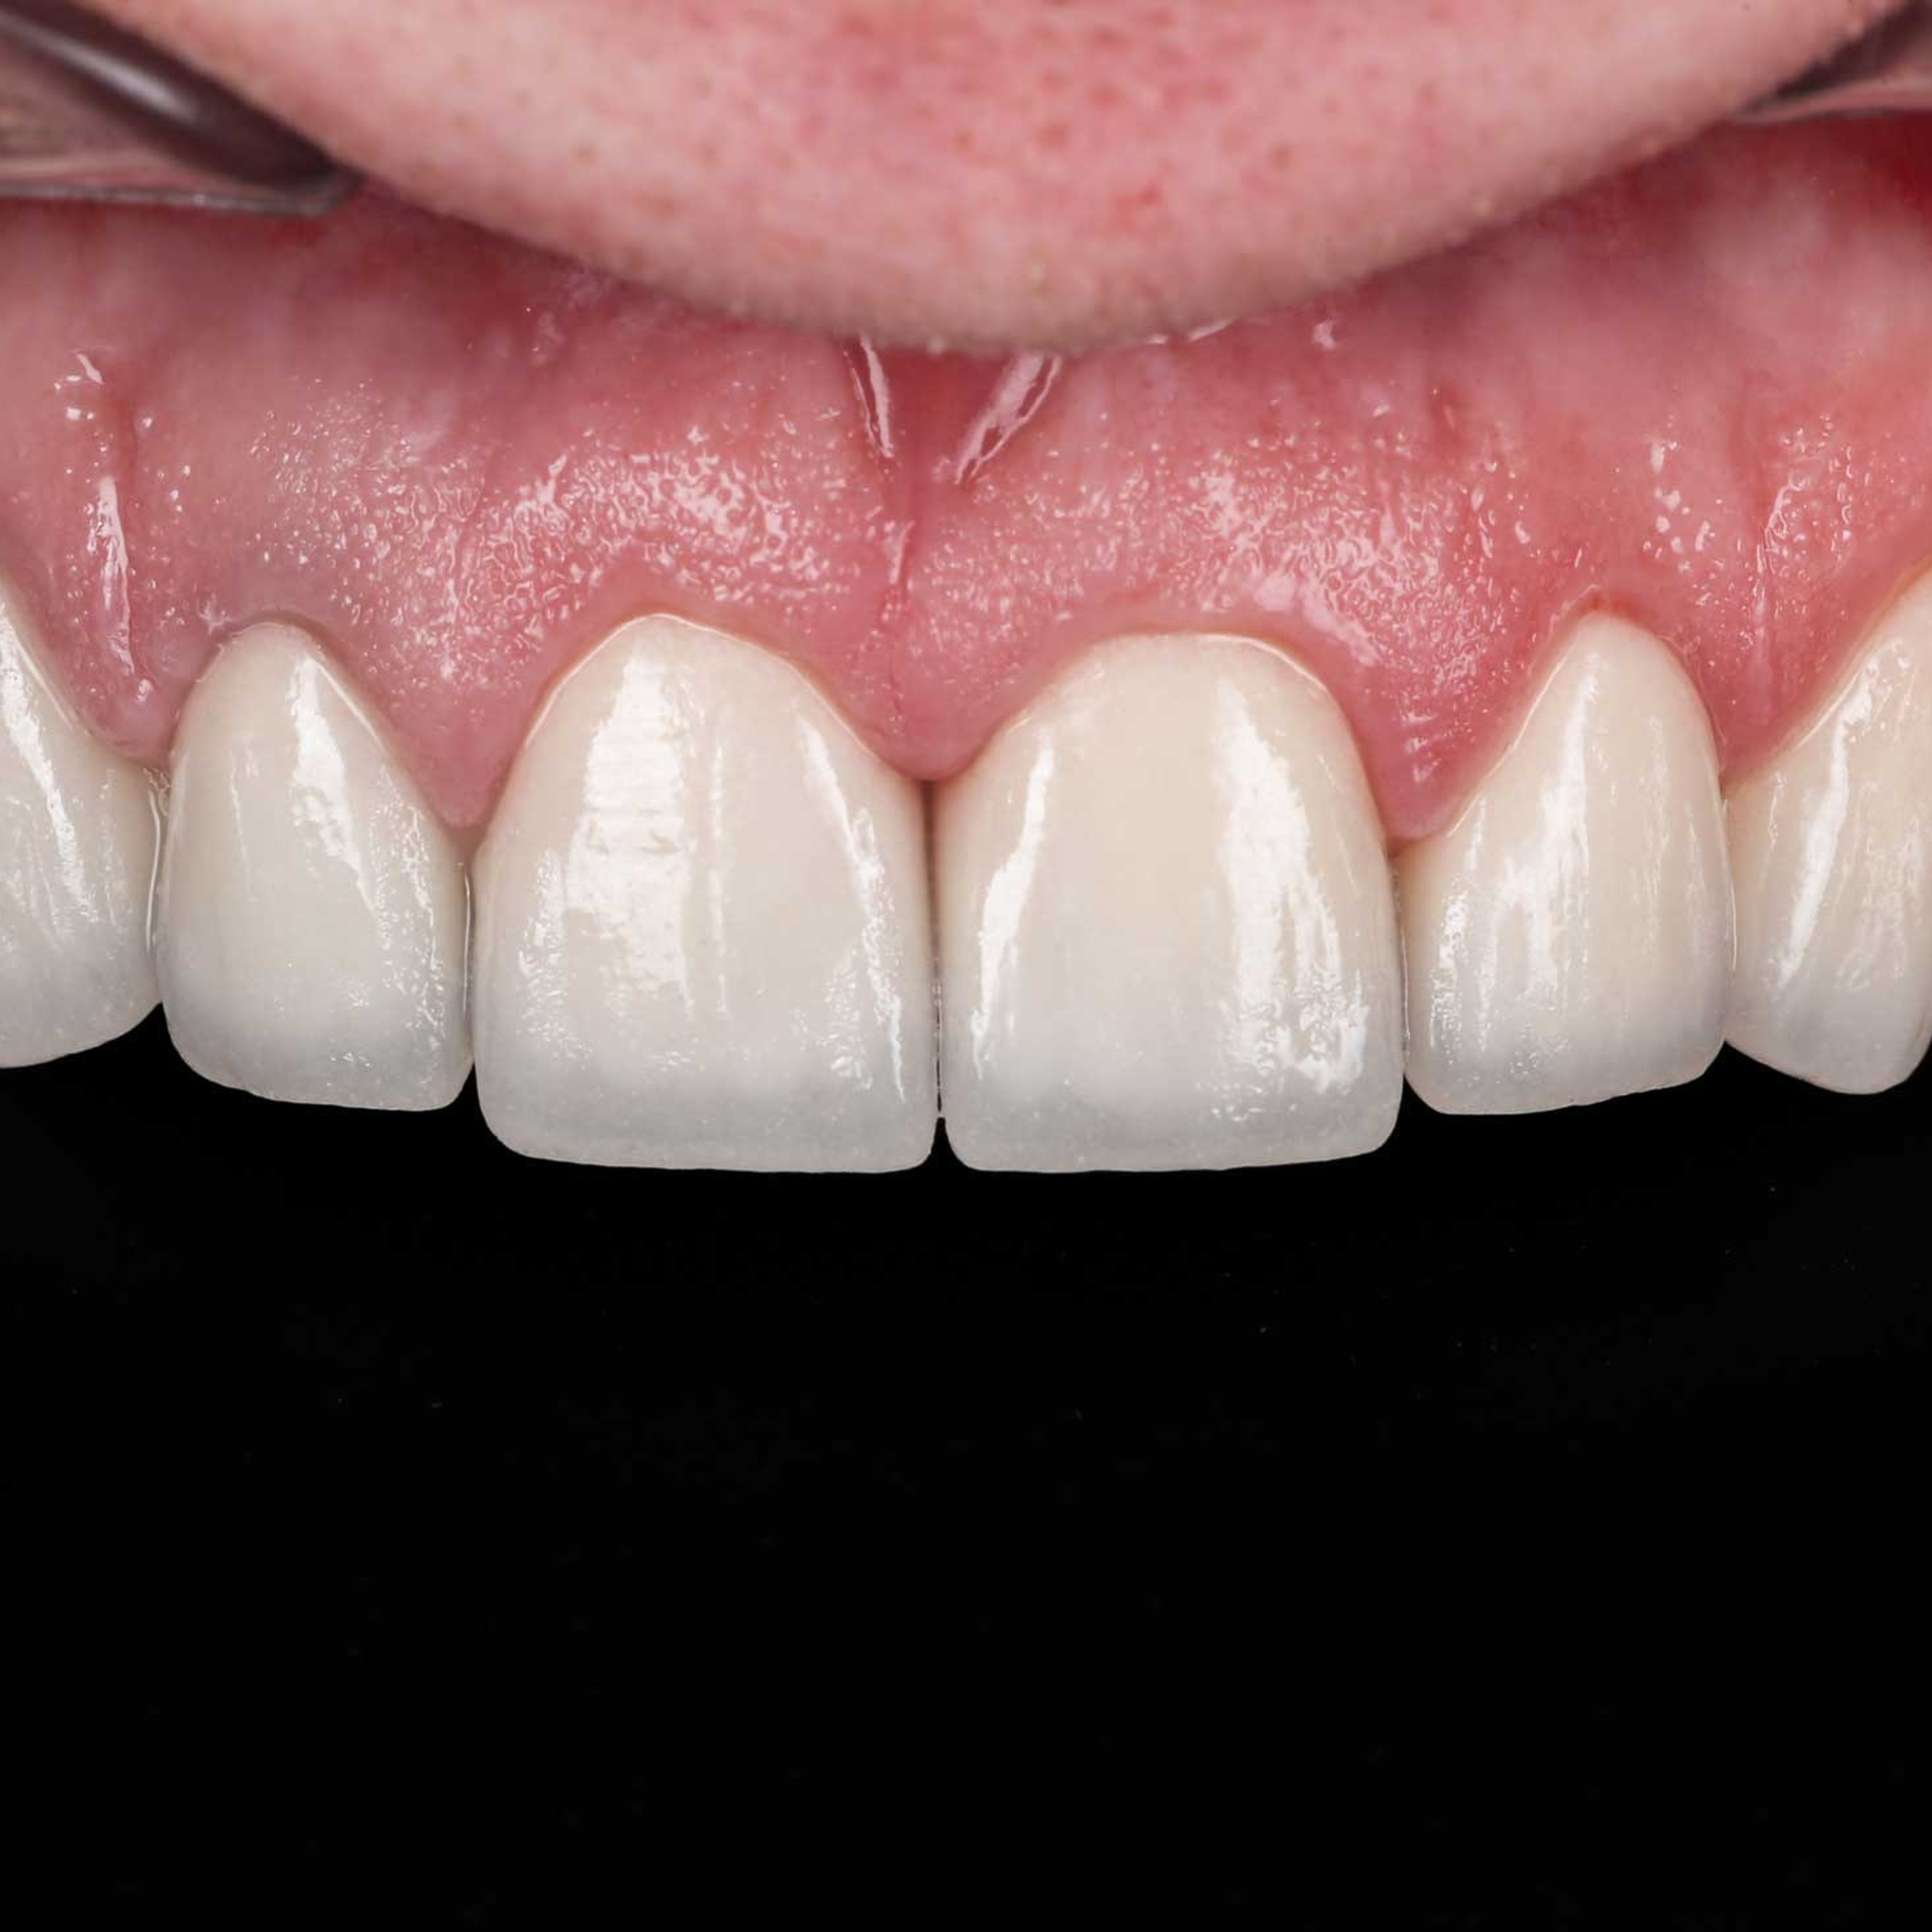

Фотографии учеников до обучения

Фотографии после обучения